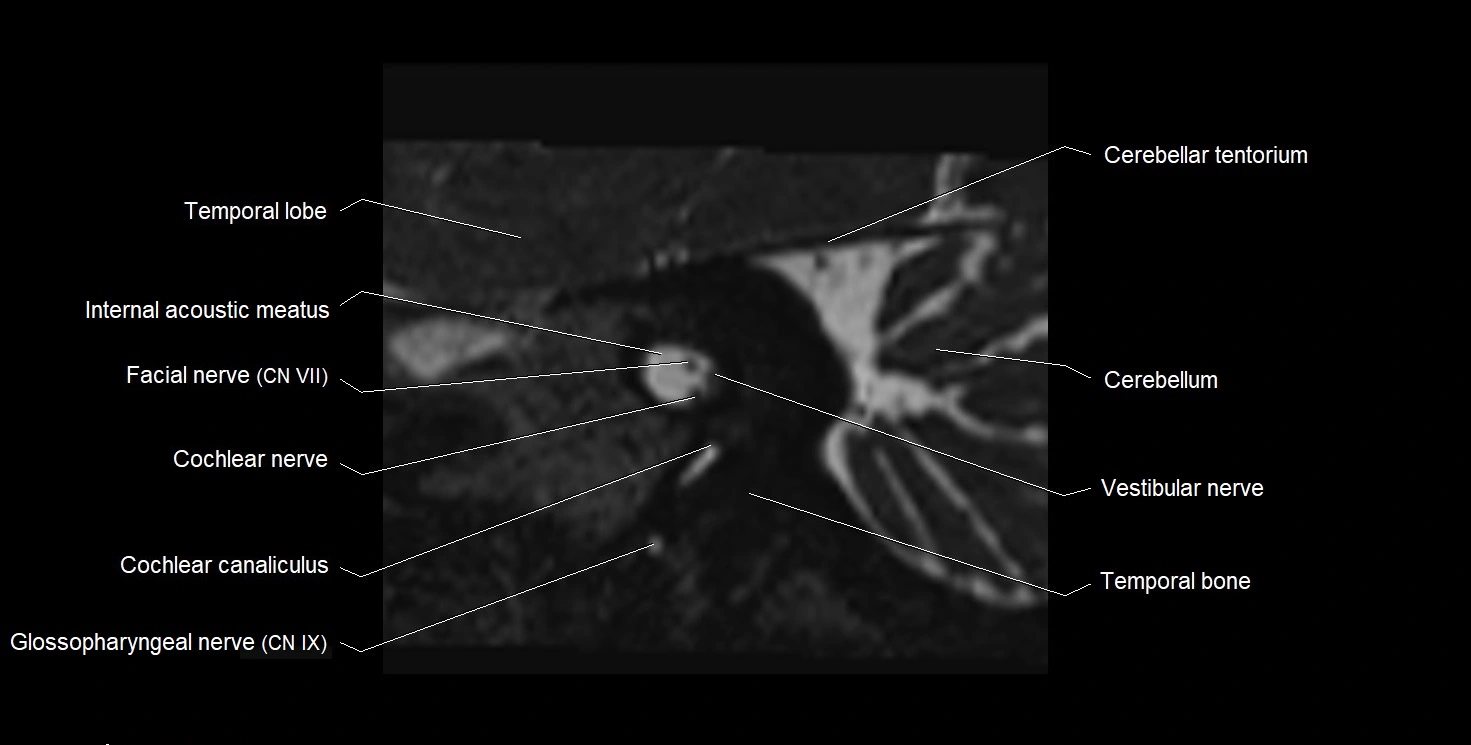

MRI images

image